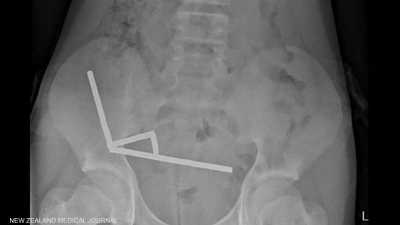

صبي يبتلع 100 مغناطيس اشتراها من "تيمو".. والشركة تعلق

l

26 أكتوبر 2025